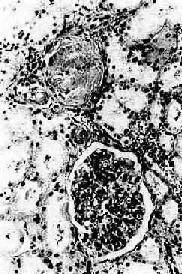

图8-12 高血压病之肾

肾小球入球小动脉管壁玻璃样变性,肾小球纤维化,玻璃样变